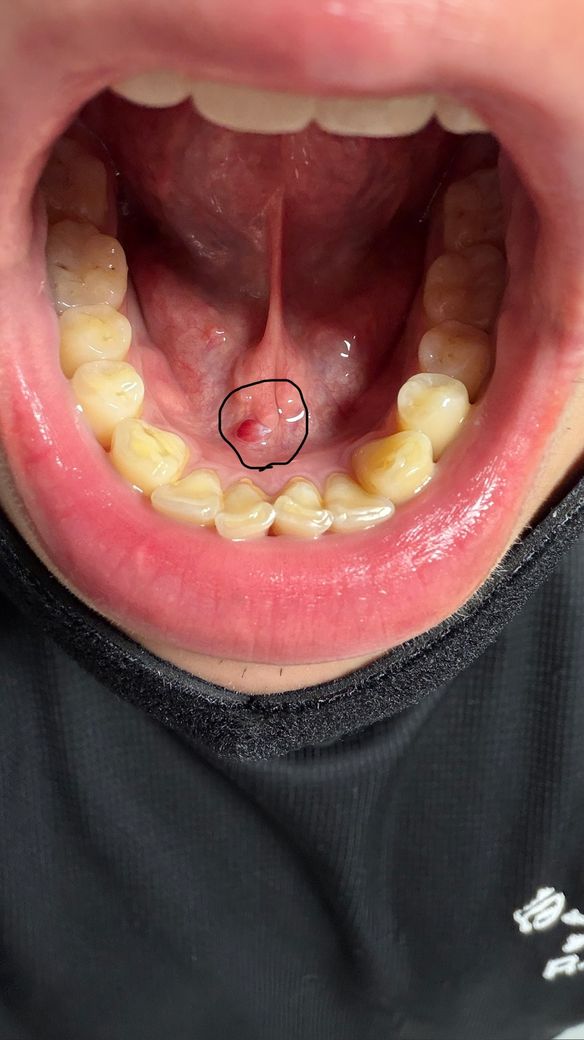

한 2~3주정도 계속 저 물집이있는데 병원가서 제거를 해야될까요?? 정체가 멀까요?ㅠ 자세히 본건 너무 무섭습니다 ㅠㅜ 답변 꼭 부탁드릴께요 ㅜㅜㅠ

날카로운 음식이나 물체에 해당 부분이 자극되어 나타난 것이 아니고 갑자기 나타났다면 구강 내 연조직 문제를 생각해보아야 합니다. 해당 위치는 타액선이 위치한 곳이므로 해당 부분의 문제가 있는지도 평가해야 합니다. 일반적인 치과가 아닌 구강내과 전문의가 상주하는 치과나 대학병원 내 구강내과를 방문해보시길 바랍니다.

혈종으로 보입니다 잘못 씹어서 생긴 상처에 피가 안에서 고인 것 같은데 정확한건 치과를 가봐야 압니다 구강내과로 가보시는 것을 추천합니다